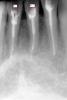

danti$t Опубликовано 19 декабря, 2010 Поделиться Опубликовано 19 декабря, 2010 Здравствуйте уважаемые коллеги, запломломбировал каналы с выведением гуттаперчивого штифта за верхушку на 1,5-2мм в 31, 33, 41, 42 зубах. Зубы под протезирование, ортопед отказывается протезировать, говорит перелечивай. До лечения зубы были интактны, силлер АН+, жалобы у пациента сразу после пломбировки и спустя уже 2 недели отсутствуют, перкуссия безболезненна.Реально ли достать гуттаперчу не оборвав этот кончик? И вообще стоит ли это делать, ведь гутта биоинертный материал, каков прогноз? Ссылка на комментарий

Снежана Опубликовано 19 декабря, 2010 Поделиться Опубликовано 19 декабря, 2010 не нужно ничего пробовать, там уже анкеров накрутили, посылайте ортопеда в сад (но очень культурно, можно на коленях))) иначе еще таких дров наломаете.у вас чего рентген в соседней деревне? снимки то с мастерштифтами делать весьма желательно.вот первый снимок еще без анкеров, и обтурация не плотная, их можно просто перелечить. эти микро.... ну не знаю, мне они к душе не пришлись, прикола не поняла. Ссылка на комментарий